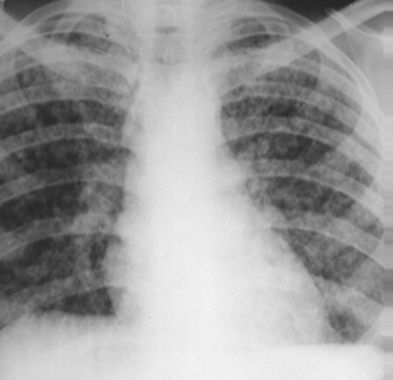

Rx toracică, incidență P-A

DESCRIERE:

pe tot teritoriul pulmonar, bilateral → opacități nodulare multiple de dimensiuni variabile, intensitate medie-mare, omogene, cu contur imprecis delim

confluente

distribuție anarhică

DX: bronhopneumonie

DD:

miliara TBC

MTS pulm hematogene